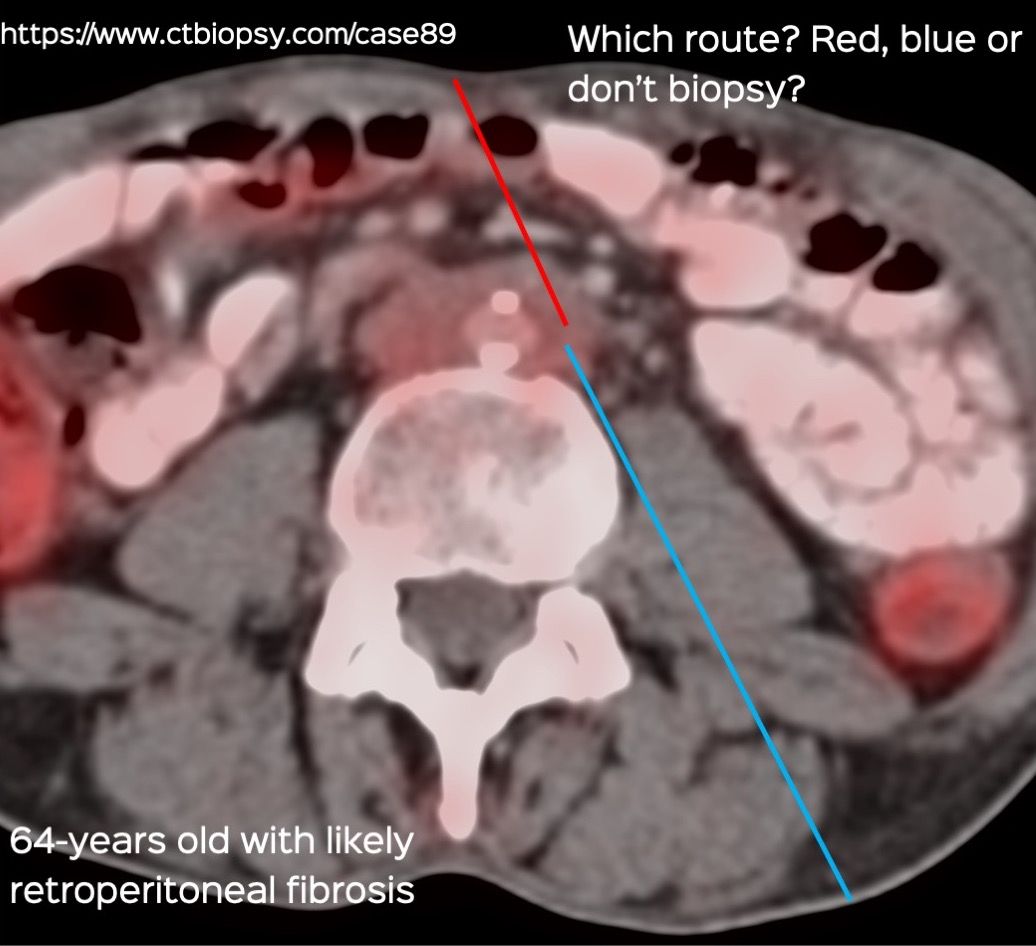

Case 89: Biopsy of Retroperitoneal Fibrosis